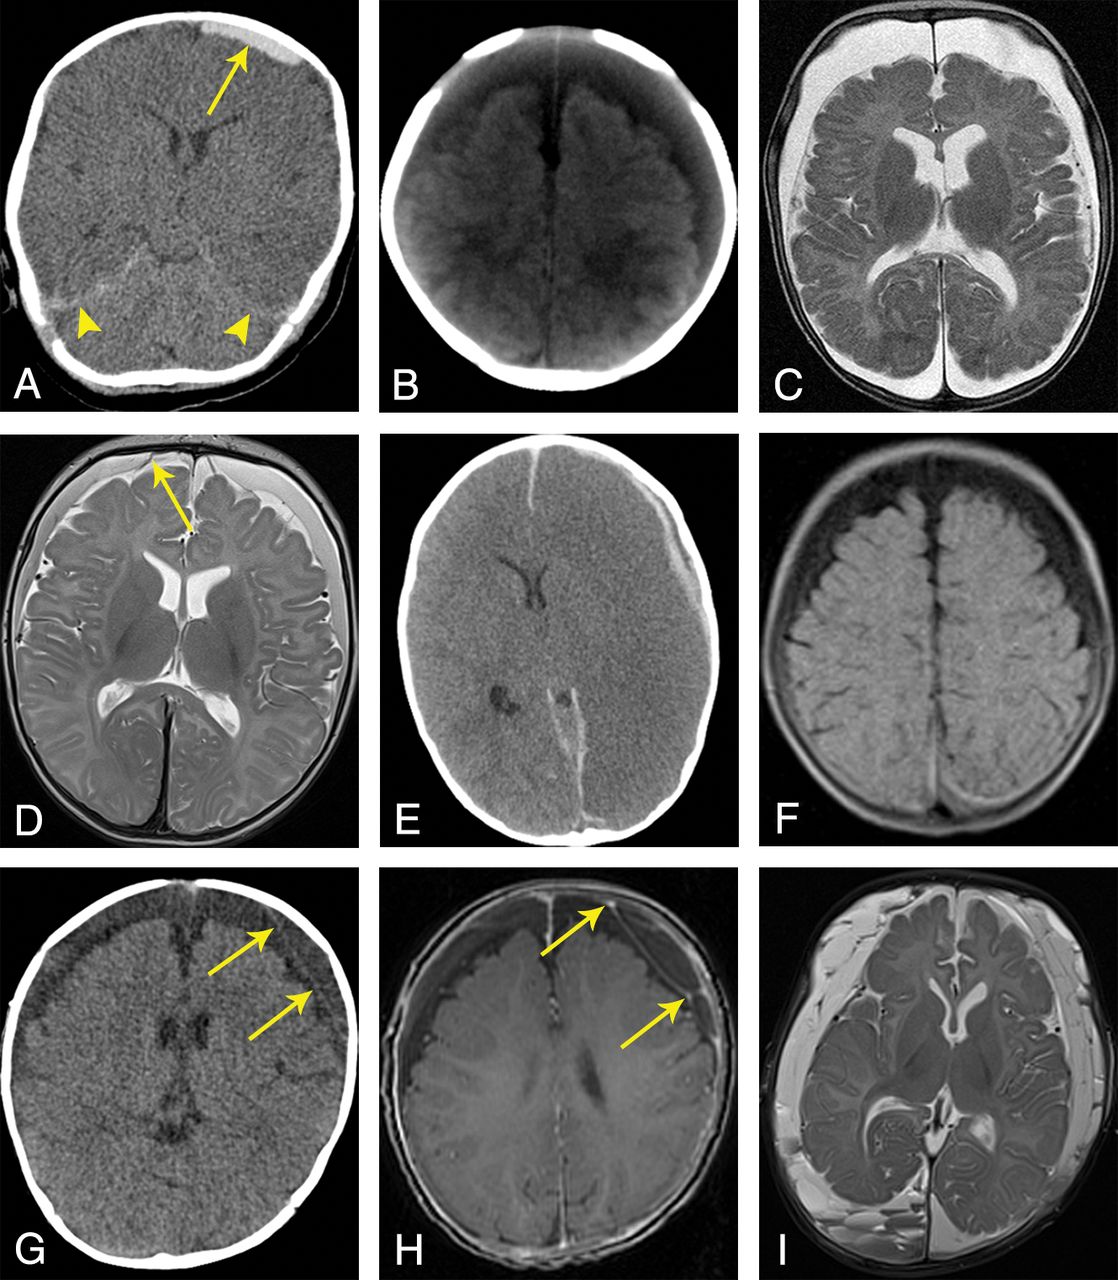

SDC entities in AHT cases. A, Acute SDH (nonenhanced CT): a 2-month-old boy with a small hyperdense SDC over the left frontoparietal region (arrow) and hyperdense blood components around the tentorium (arrowheads). B, SDHy (nonenhanced CT): a 2-month-old boy with wide, homogeneously hypodense (or CSF-isodense) SDCs over both frontoparietal regions; no neomembranes or septa. C, SDHy (MR imaging, T2WI, TSE, nonenhanced): a 4-month-old boy with wide, homogeneously CSF-isointense SDCs over both frontoparietooccipital regions, markedly frontal due to the supine position; no neomembranes or septa. D, SDHHy, homogeneous variant (MR imaging, T2WI, TSE, nonenhanced): a 3-month-old boy with homogeneous SDCs over both frontoparietal regions. Compared with CSF within the external and internal CSF spaces, the SDCs appear hypointense. Two intact BVs can be found next to the superior sagittal sinus (arrow shows 1 BV). E, SDHHy, heterogeneous variant (nonenhanced CT): a 19-month-old boy with an SDC in the left frontoparietal region. The SDC is composed of a thin, brain-sided, hyperdense component and a thin, dura-sided, hypodense component that runs parallel to the former component (mixed-density pattern). In this case, the study also revealed severe brain edema with a midline shift to the right side as well as hyperdense blood components within the anterior and posterior interhemispheric fissures. F, SDHHy, heterogeneous variant (MR imaging, FLAIR, nonenhanced): a 4-month-old girl with wide SDCs over both frontoparietooccipital regions. While the frontoparietal SDC proportions appear hypointense, the parietooccipital proportions are iso- to hyperintense. The transitional zone between the 2 components is almost smooth; fluid-fluid levels cannot be recognized unambiguously. G, Chronic SDH (nonenhanced CT): a 7-month-old boy with wide, hypodense SDCs over both frontoparietal regions and subtle formation of subdural neomembranes on the left side (arrows). H, Chronic SDH (MR imaging, T1WI, gradient-echo sequence, enhanced by contrast agent): same case as in G. Confirmation of the presence of subdurally located septa and chamber formations. In contrast to the nonenhanced T1WI (not shown), this contrast agent–enhanced study revealed focal signal enrichment located at the neomembranes (arrows). I, Chronic SDH (MR imaging, T2WI, TSE, nonenhanced): a 4-month-old boy with numerous subdural septa and neomembranes. Note the different signal intensities and multiple fluid-fluid levels within subdural chamber formations, especially in the right occipital region.

In the context of AHT, subdural hematoma (SDH) is described as the most common intracranial pathology in infants and toddlers.20⇓–22 SDHs, like all SDCs, may occur unilaterally or bilaterally.23 The convexities of the cerebral hemispheres (Fig 1A), the falx cerebri, the tentorium cerebelli, and the middle and posterior cranial fossae are considered typical locations.22 In many cases, SDHs have a key role as a diagnostic marker only—that is, though they may represent an important symptom of child abuse, their volumes are often small, resulting in just a minor space-occupying effect.8,21,23⇓–25 Hence, frequently, SDHs do not have a prognostic relevance for the extent of brain damage.24 Depending on the developmental stage in which subdural blood is visualized by neuroimaging, SDHs have a wide variety of appearances (Table 1). The chronic SDH has a special position (see below: “Chronic Subdural Hematoma”).

Currently, from the pathophysiologic point of view, chronic subdural hematoma (cSDH) is considered a separate SDC entity.23 cSDH denotes a serosanguinous, petroleum-, or crankcase-like fluid collection surrounded and sometimes loculated (divided into compartments) by neomembranes (Fig 1G, -I).26,33⇓–35 Neomembranes contain numerous new blood vessels leading to accumulation of contrast agent in neuroimaging studies.22,27 The presence of neomembranes represents an important criterion for distinguishing cSDH and SDHy. In contrast to the situation in adults, genuine cSDHs are relatively rare in infants.22,36⇓–38

The term subdural hygroma (SDHy) is classically reserved for proteinaceous, clear, pink-tinged, or xanthochromatic collections within the subdural space containing pure CSF or at least CSF-like fluid; blood, blood products, or neomembranes are nonexistent by definition (Fig 1B, -C).22,26,27 However, the smallest amounts of blood within the SDHy cannot always be excluded and may become noticeable on CT by a slightly higher density compared with CSF (see below: “Subdural Hematohygroma,” “homogeneous variant”).

Subdural hematohygromas (SDHHys) are a combination of blood (or blood products) and CSF (or CSF-like fluid).22,28⇓–30 A homogeneous and a heterogeneous variant can be differentiated.

In many cases of an SDC diagnosed as SDHy, it may be assumed that the SDC is actually the homogeneous variant of the SDHHy (Fig 1D) because the blood component may sometimes be relatively small and/or very “young” (hyperacute); furthermore, an intense mixture of blood and CSF may be present.27⇓–29 Hence, in our experience, SDHy and SDHHy are used interchangeably or synonymously in radiology reports.

The heterogeneous variant of the SDHHy (Fig 1E, -F) indicates 2 SDC components that coexist within the same subdural compartment (eg, above a brain convexity); these components may be clearly distinguished from one another (fluid-fluid levels possible) and may appear hyper- and hypodense during CT investigations (mixed-density pattern).22,28,30⇓–32 The hypodense component is interpretable as the following:

Mixed-Density SDCs: Repeated Trauma?

In initial CT investigations, SDCs frequently show a mixture of hyper- and hypodense proportions (so-called mixed-density pattern) (Fig 1E). This pattern is significantly more frequent in AHT than in accidental head trauma.30,72 In the past, the dogma was that such a pattern would represent a combination of “new” and “old” blood, indicating repeated trauma. Today, this view has changed. At least 4 different scenarios have been proposed as explanations for the mixed-density pattern, and 3 of them may be deduced from only 1 single traumatic event (Table 2, upper part).22,28

Hypodense Subdurals: Acute or Chronic?

The presence of isolated iso- to hypodense SDCs is another typical problem in CT investigations of SDCs (Fig 1B). At least 5 possibilities of interpretation, besides SDHy and SDHHy, compose nearly all time-related SDH stages from hyperacute to chronic (Table 2, lower part).22 Hence, a reliable diagnosis and age estimation of the SDC are frequently not possible without additional MR imaging and serial neuroimaging, respectively. The diversity of differential diagnoses shown in Table 2 illustrates that the diagnosis of a chronic process (cSDH) may be hasty.

Finally, in many cases, the question is whether the diagnosis is SDHy or cSDH. While the former is compatible with both a rapid and a delayed process, the latter, in fact, suggests a traumatic event that occurred weeks ago. Several distinguishing criteria have been proposed (Table 3) to address this question.22,27⇓–29,33,66,74 The most important criterion is the presence of subdural neomembranes, septa, or chamber-like formations characterizing cSDHs. In neuropathology, the first formation of neomembranes is described as macroscopically visible after ∼10 days.74 Their radiologic detection may be challenging and often requires MR imaging, sometimes even supported by intravenous contrast. In those cases, the presence of neomembranes is described after ∼2–4 weeks.22